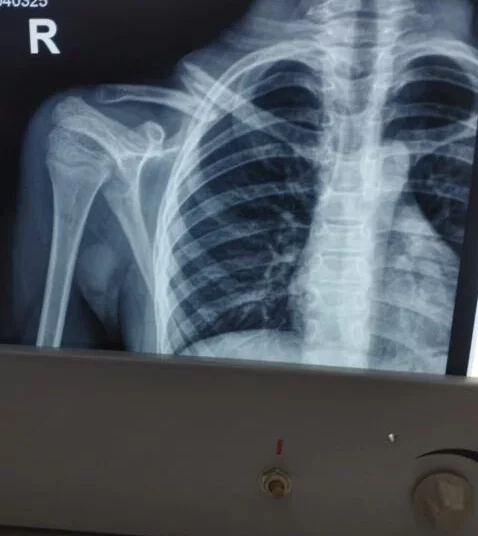

релом Ключицы У Ребенка Фото

Перелом Ключицы У Ребенка Фото 111 фотографий